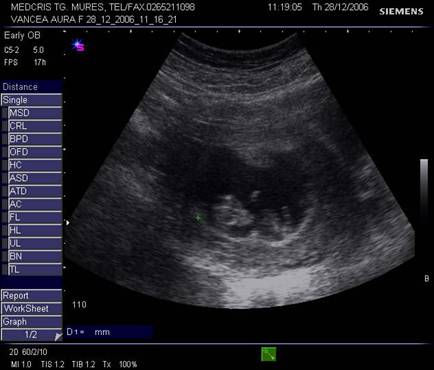

Fig nr. 8. Sarcina 5 sapt la ecografia transvaginala :sac ovular cu vezicula vitelina evidenta marcata cu sageata, retrouterin ovar chistic